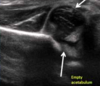

How does transient synovitis present and what investigations should you do for this?

A

Presentation

• History of URTI

• Low grade fever (if high think septic)

• Limp

• Refusal to weight bear

• Groin or hip pain

Ix

• FBC: look at WCC

• CRP

• US and X-ray: look for effusion

• Joint aspirate: if considering septic, send for MC+S